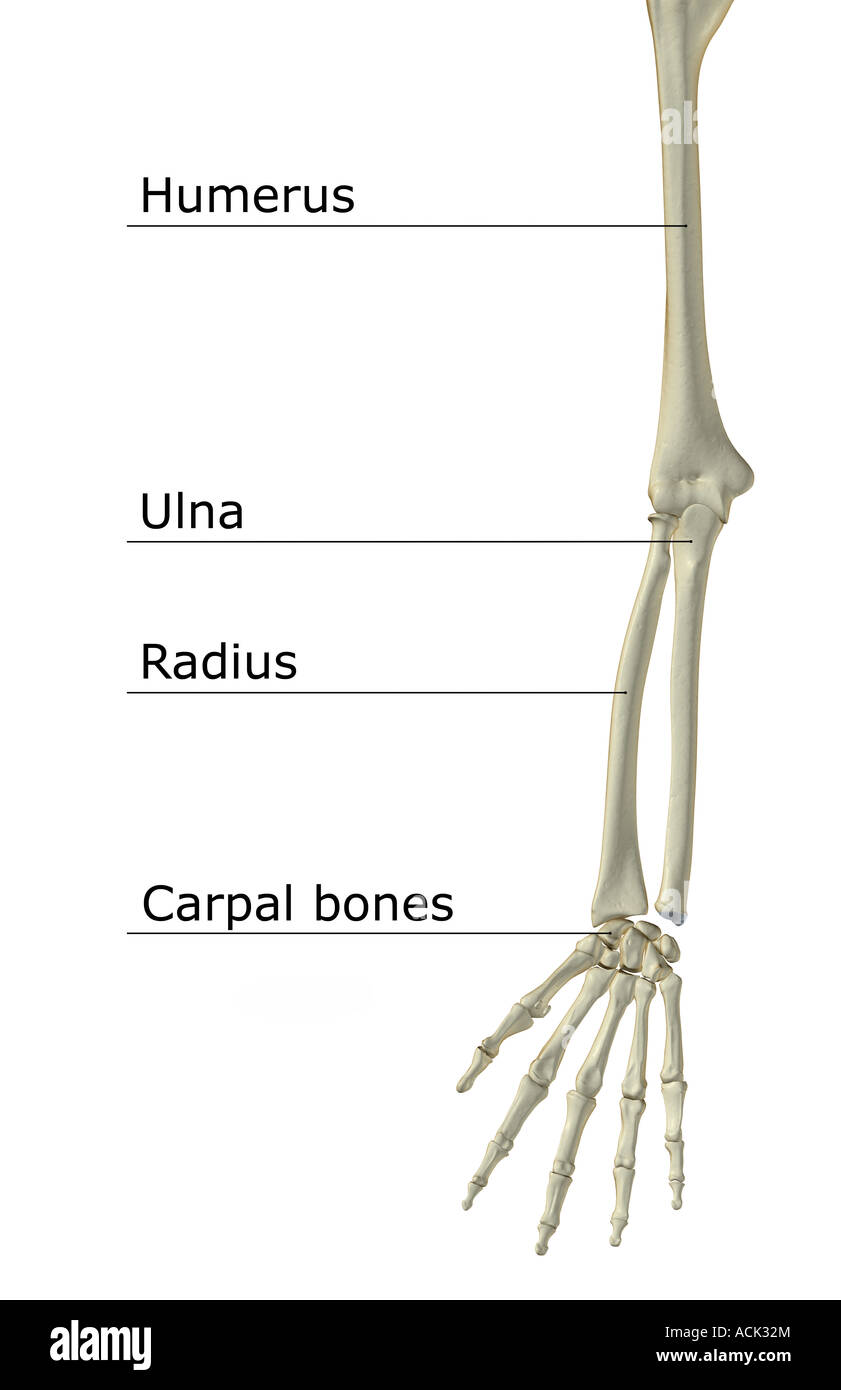

RF2JNYJM7–Präzise Knochen des Arms oder der oberen Extremität des menschlichen Skelettsystems oder Skeletts isoliert auf weißem Hintergrund 3D Rendering Illustration. Anterior und